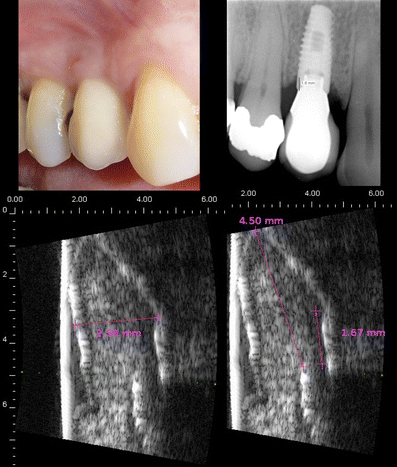

2. ارزیابی تحلیل استخوان اطراف ایمپلنت:

با استفاده از سونوگرافی میتوان سطوح تماس استخوان و ایمپلنت را بررسی کرده و تحلیلهای مارجینال را بدون نیاز به اشعه پایش کرد.

سونوگرافی امکان تشخیص ضایعات زیرسطحی، کیستها، فیستولها و نواحی عفونی اطراف ایمپلنت را با دقت بالا فراهم میکند.